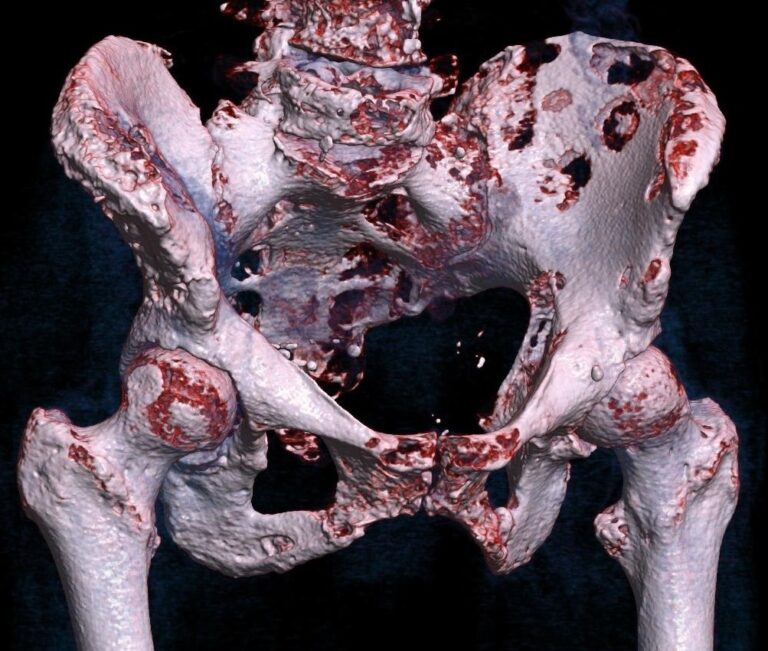

Kosti s nádorem: Zhoubným bujením trpěli lidé už v pravěku

Rakovina jako moderní civilizační nemoc? Omyl, ani zdání. Četné výzkumy nalezených ostatků z pravěku a starověku vydávají jasné svědectví. Rakovina tu byla s námi už před 120 tisíci lety. V roce 2013 objevila Michaela Binderová, doktorandka z Durhamské univerzity ze severovýchodní Anglie, v Súdánu na břehu řeky Nil ostatky 25–35 letého muže. Kostra obsahovala i metastázující rakovinný nádor. „Tohle […]